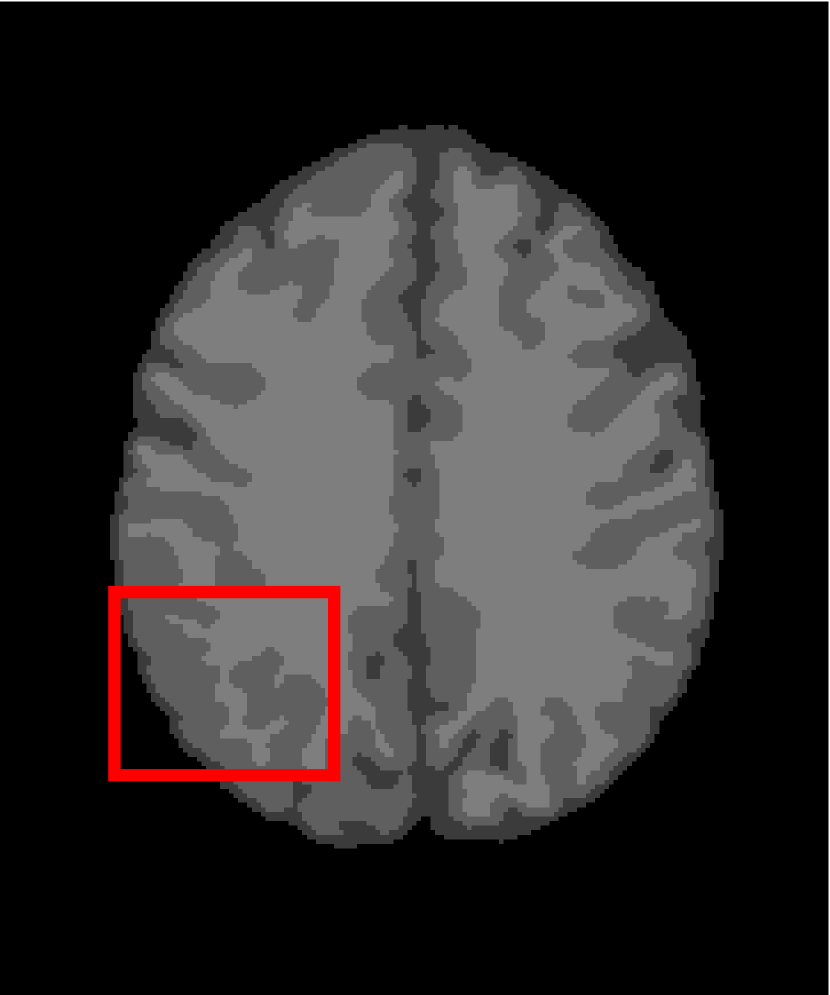

In the second experiments, we segment two medical images coming from a simulated brain database (BrianWeb): http://www.bic.mni.mcgill.ca/brainweb/. The two images are generated by T1 modality with slice thickness of 1mm resolution, 9% noise and 20% intensity non-uniformity. Here, the two images are represented two slices in the axial plane with the sequence of 100 and 110. Moreover, there are golden standard segmentations in the dataset. We set the numbers of clusters to 4. The visual comparisons are illustrated in Figs. 6 and 7.

Figure 7: Segmentation results for the second medical image. From (a) to (l): ground truth, noisy image and results of FCM_S1, FCM_S2, FGFCM, FLICM, KWFLICM, ARKFCM, FRFCM, WFCM, DSFCM_N, and LRFCM.

By focusing on the marked red square in Figs. 6 and 7, we easily find that FCM_S1, FCM_S2, FGFCM and ARKFCM are sensitive to noise. FLICM and KWFLICM are vulnerable to severe intensity inhomogeneity. FRFCM brings overly smooth results due to the use of gray level histograms. WFCM and DSFCM_N cause several contours to change. However, LRFCM acquires clear contours and suppresses noise adequately. Moreover, we find that the segmentation result of LRFCM is closer to ground truth.